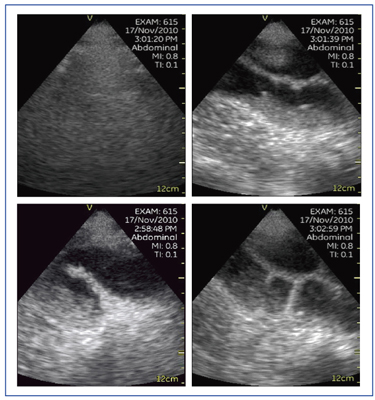

救急時における代表的な症例として,腎結石,腸閉塞,肝膿瘍を挙げることができる(図8〜10)。腸閉塞症例は,ハイエンド装置にて内容液と腹水が認められた。Vscanで検査を行う際のポイントは,静止画に加えて必ず動画を記録することである。動画によって腹水の動きが観察可能である(図9)。

図9 症例4:腸閉塞

図10 症例5:肝膿瘍